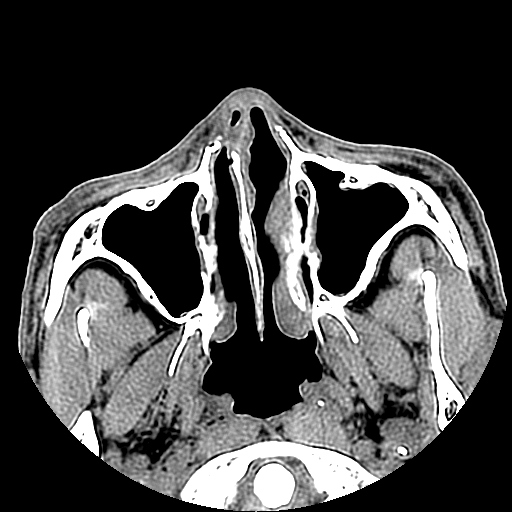

以下是引用liaoqiang在2008-7-16 21:15:00的发言:[br]右侧鼻骨骨折

以下是引用zxd95在2008-7-16 21:39:00的发言:[br]右侧上颌骨额突骨折。[br][br][br][br]